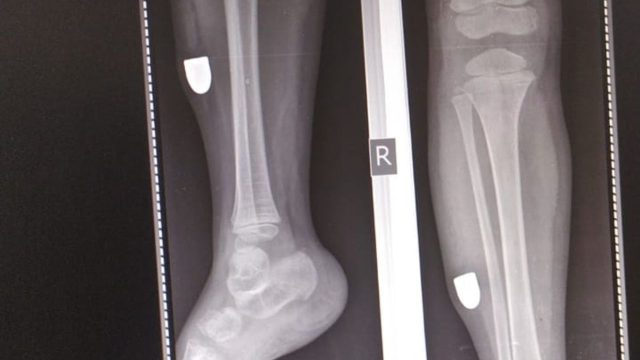

ਪਰਿਵਾਰਕ ਮੈਂਬਰ ਮੰਗਲਵਾਰ ਸ਼ਾਮ 4 ਵਜੇ ਬੱਚੀ ਨੂੰ ਨੇੜਲੇ ਟਿਊਸ਼ਨ ਸੈਂਟਰ ਛੱਡਣ ਜਾ ਰਹੇ ਸਨ। ਇਸ ਦੌਰਾਨ ਇਹ ਘਟਨਾ ਵਾਪਰੀ। ਇਸ ਘਟਨਾ ਬਾਰੇ ਪੁਲਿਸ ਨੂੰ ਸੂਚਿਤ ਕੀਤਾ ਗਿਆ ਹੈ। ਗੋਲੀ ਲੱਗਣ ਦੀ ਜਾਣਕਾਰੀ ਉਦੋਂ ਮਿਲੀ ਜਦੋਂ ਉਸਨੂੰ ਹਸਪਤਾਲ ਲਿਜਾਇਆ ਗਿਆ ਅਤੇ ਡਾਕਟਰਾਂ ਨੇ ਐਕਸ-ਰੇ ਕਰਵਾਇਆ। ਉਦੋਂ ਪਤਾ ਲੱਗਾ ਕਿ ਬੱਚੀ ਦੀ ਲੱਤ ਵਿੱਚ ਗੋਲੀ ਲੱਗੀ ਹੈ।

ਮੰਗਲਵਾਰ ਸ਼ਾਮ ਨੂੰ, ਜਦੋਂ ਉਹ ਵ੍ਰਿਧੀ ਨੂੰ ਉਸਦੀ ਟਿਊਸ਼ਨ ਛੱਡਣ ਜਾ ਰਹੇ ਸਨ, ਤਾਂ ਉਸਦੀ ਲੱਤ ‘ਤੇ ਸੱਟ ਲੱਗ ਗਈ। ਜਦੋਂ ਵ੍ਰਿਧੀ ਨੇ ਉਨ੍ਹਾਂ ਨੂੰ ਆਪਣੀ ਲੱਤ ‘ਤੇ ਸੱਟ ਬਾਰੇ ਦੱਸਿਆ ਅਤੇ ਇਸਦੀ ਜਾਂਚ ਕੀਤੀ ਗਈ, ਤਾਂ ਅਜਿਹਾ ਲੱਗਿਆ ਜਿਵੇਂ ਕੋਈ ਜ਼ਖ਼ਮ ਹੋਵੇ ਅਤੇ ਖੂਨ ਵਗ ਰਿਹਾ ਹੋਵੇ। ਪਰਿਵਾਰਕ ਮੈਂਬਰ ਉਸਨੂੰ ਹਸਪਤਾਲ ਲੈ ਗਏ। ਜਦੋਂ ਉੱਥੇ ਉਸਦਾ ਐਕਸ-ਰੇ ਕੀਤਾ ਗਿਆ ਤਾਂ ਪਤਾ ਲੱਗਾ ਕਿ ਉਸਦੀ ਲੱਤ ਵਿੱਚ ਗੋਲੀ ਲੱਗੀ ਸੀ। ਕੁਝ ਸਮੇਂ ਬਾਅਦ, ਲੜਕੀ ਦਾ ਆਪ੍ਰੇਸ਼ਨ ਕੀਤਾ ਗਿਆ ਅਤੇ ਗੋਲੀ ਕੱਢ ਲਈ ਗਈ। ਗੇਟ ਹਕੀਮਾਨ ਪੁਲਿਸ ਸਟੇਸ਼ਨ ਦੇ ਇੰਚਾਰਜ ਇੰਸਪੈਕਟਰ ਮਨਦੀਪ ਕੌਰ ਨੇ ਕਿਹਾ ਕਿ ਮਾਮਲੇ ਦੀ ਜਾਂਚ ਕੀਤੀ ਜਾ ਰਹੀ ਹੈ।